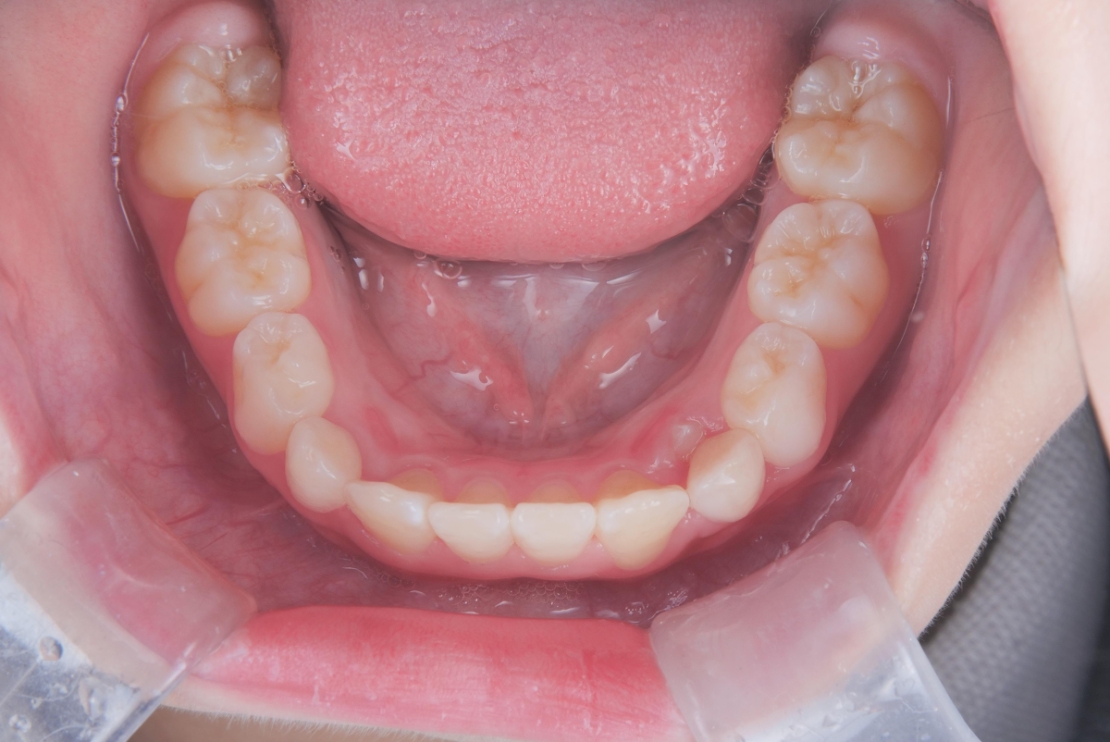

AFTER

治療は、マウスピース矯正インビザライン・ファーストにて矯正治療を行い、成長を活かしながら歯列と噛み合わせを整えていきました。治療期間は1年2ヶ月で、ガタつきと深い噛み合わせが改善し、将来を見据えた安定した歯列環境を整えることができました。

成長期だからこそ可能なアプローチで、早期に問題を改善できた症例です。